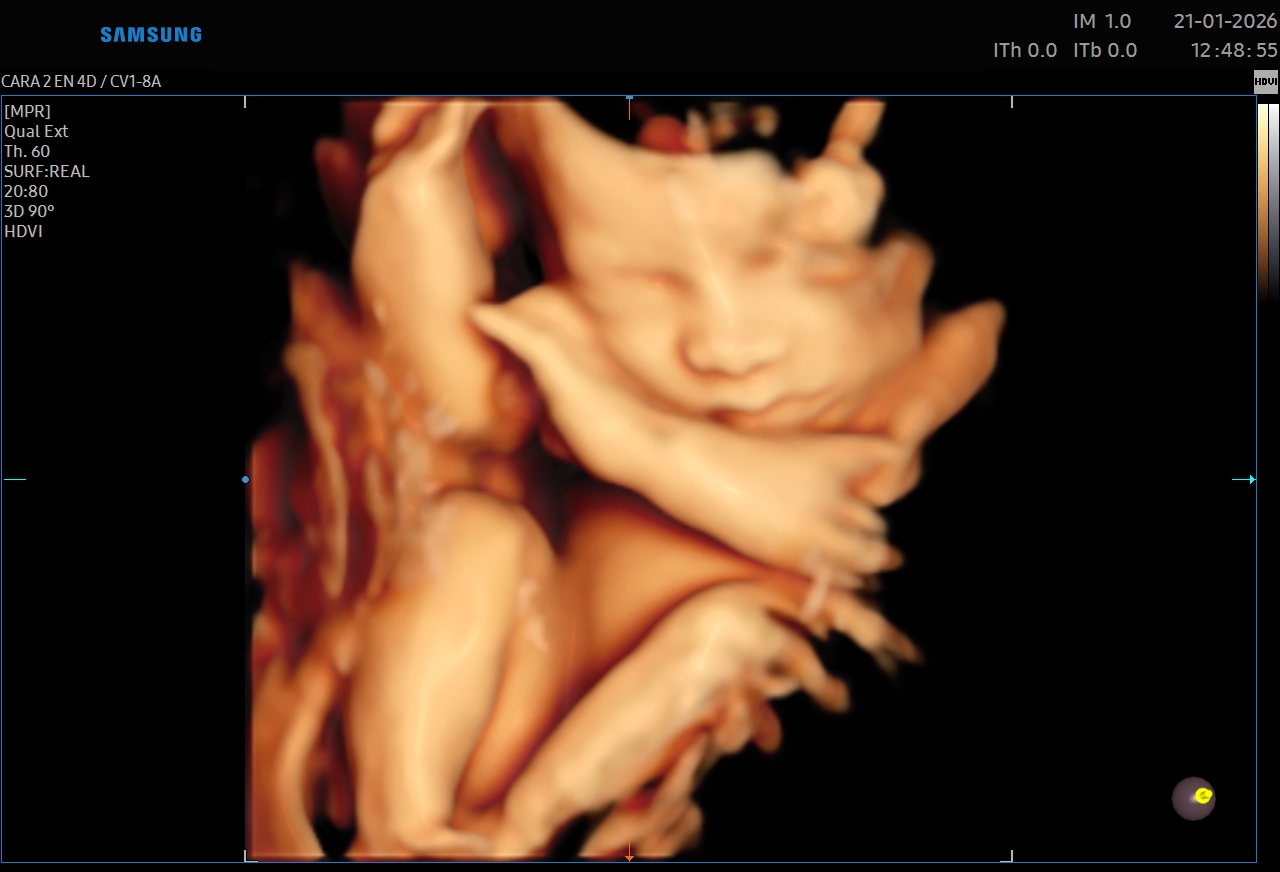

Ecografías 5D

La ecografía 5D es una experiencia única que te permite ver a tu bebé con un nivel de realismo sorprendente, capturando detalles como sus gestos, expresiones y movimientos en tiempo real.

Gracias a esta tecnología avanzada, podrás observar el rostro de tu bebé con mayor claridad, creando un vínculo emocional aún más especial antes de su nacimiento. Es el momento perfecto para compartir con tu familia y guardar recuerdos inolvidables de esta etapa tan importante.

Además de ser una experiencia hermosa, este estudio se realiza con equipos de alta tecnología y bajo supervisión médica, garantizando seguridad tanto para la mamá como para el bebé.